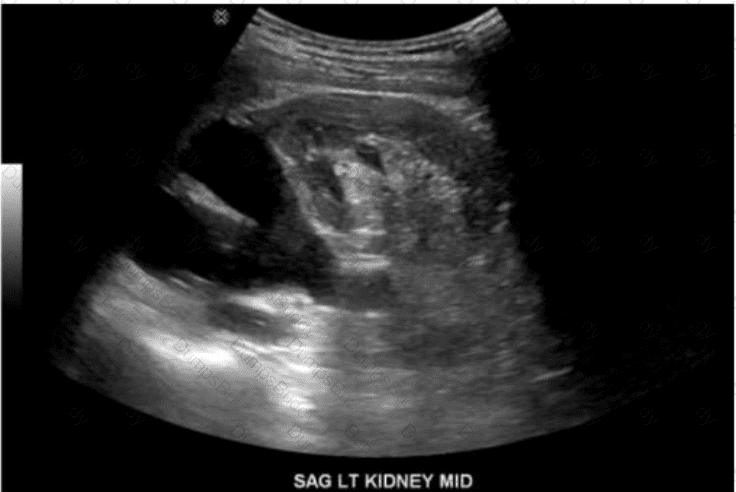

Which congenital disorder is most consistent with the finding identified by the arrow on this image?